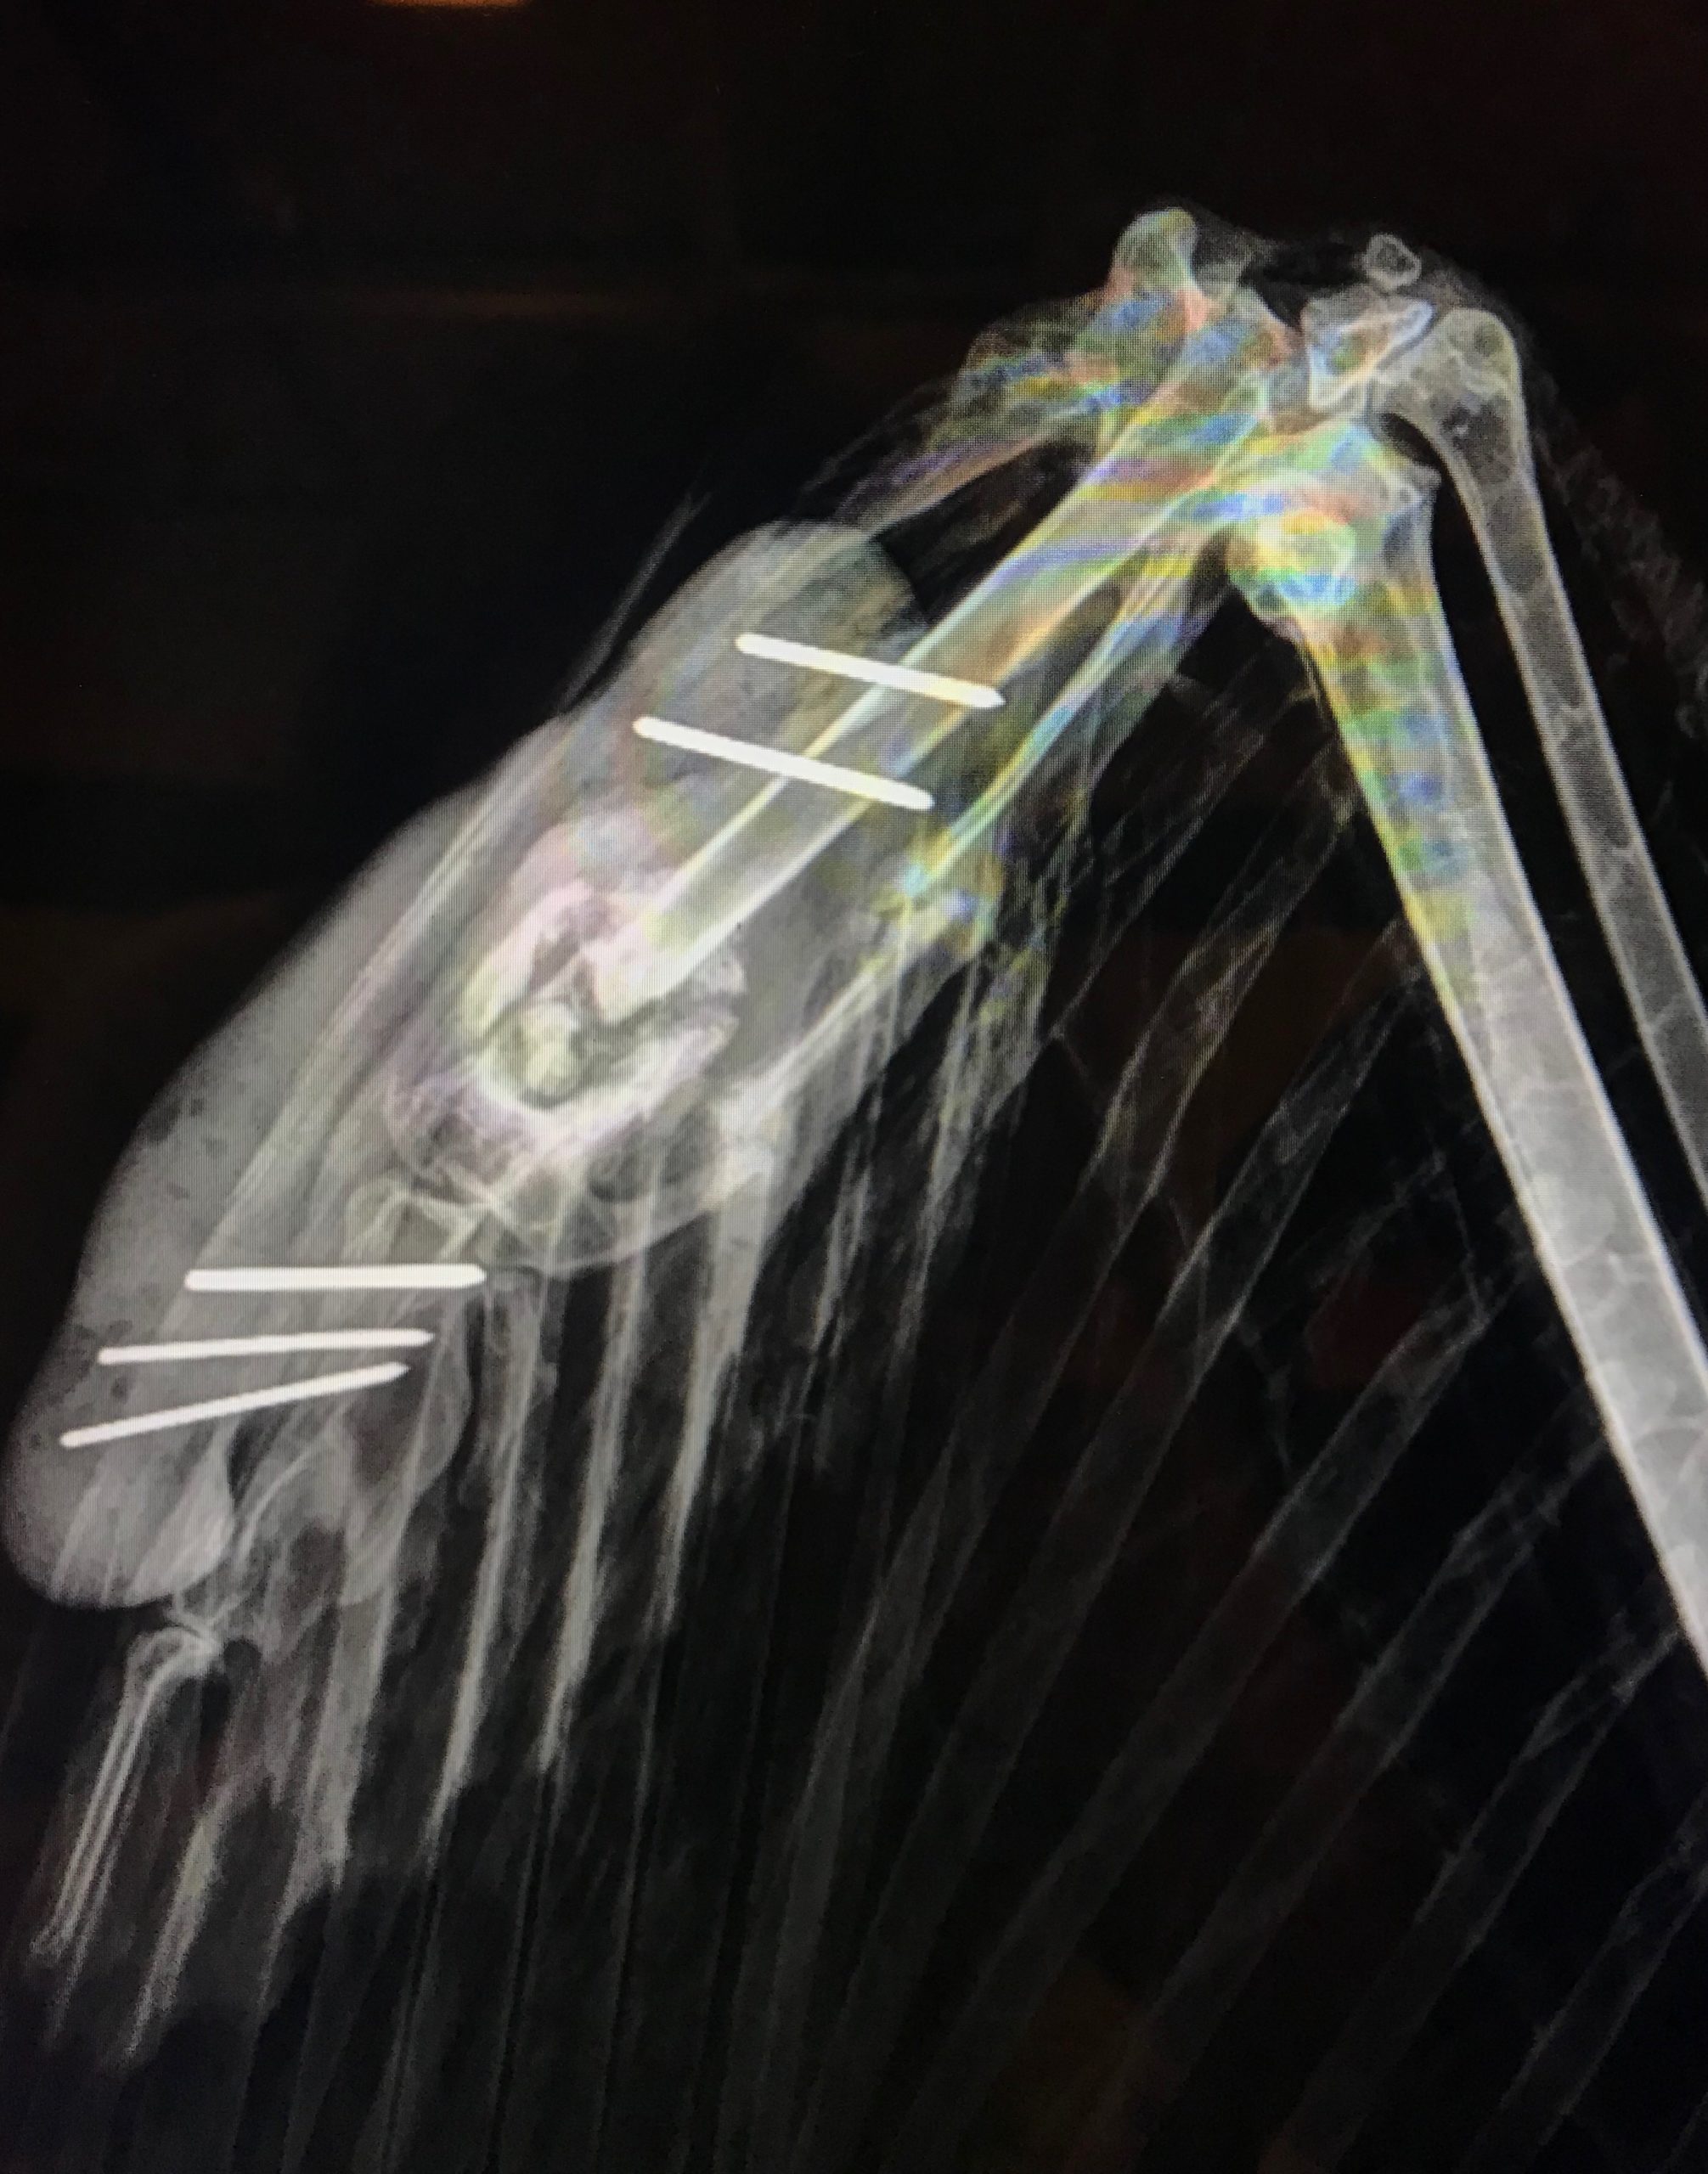

During transport, the eagle re-fractured the major metacarpal bone in an attempt to escape, resulting in a new open wound. We absolutely expect an otherwise healthy wild predator to behave this way in captivity, which is a huge part of the challenge when treating them. As it turns out, the callus had formed around necrotic (dead) bone tissue in the major metacarpal bone which was impossible to tell from the initial radiographs. It was fortunate that we were able to take her back in address the fracture as it may not have been able to get back enough strength to allow the bird to get back to full hunting capacity in the wild. The team initially took recheck radiographs to assess the extent of the new fractures, and a plan was made for surgical repair.

It was not until the site was accessed surgically that the necrotic debris could be accessed and removed. In place of this necrotic bone, fragments from the bird’s keel (‘breast’) bone were grafted into the metacarpal bone and pins were also surgically placed above and below the fracture site in order to better stabilize the fragile area.

Radiographs taken after the surgery indicated that the pins were in the proper positions to stabilize the fracture. In this radiograph, you can also see the antibiotic beads that are still in place to allow targeted release of medication to the area. The skin surrounding the open wound was not suitable to suture closed, so the team is managing the wound with medicinal honey and daily bandage changes. Manuka honey works as a natural antibiotic and will protect the area while the skin heals. This bald eagle actively attempts to evade capture for her daily bandage changes and is appropriately feisty, and we hope that with this treatment plan, a much more stable callus will form and we will continue to see progress with this patient!